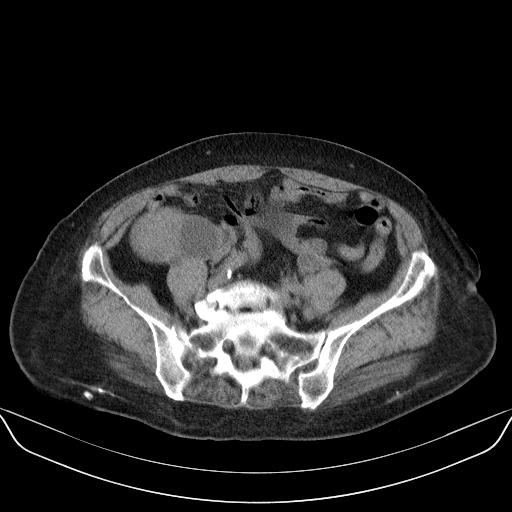

以下是引用yuhongjun在2010-3-12 6:32:00的发言:[br]回肠末端间质瘤,不除外阑尾粘液囊腺瘤,臀部注射性肉芽肿钙化. [br] [br]